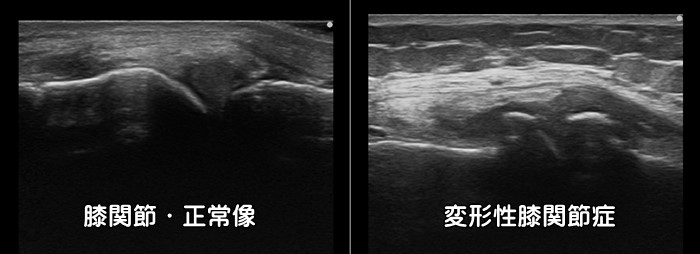

変形性膝関節症

膝の内側の痛みがあれば変形性膝関節症を疑います。軟骨がすり減り、骨が変形します。

エコー検査では変形の有無・炎症の有無を確認できます。